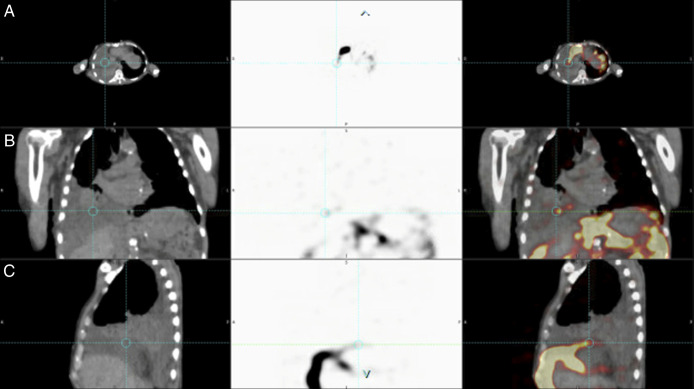

Index Hepatic Decompensation: Hepatic Hydrothorax Without Signs of Clinically Significant Portal Hypertension Diagnosed With Radioisotope Scintigraphy.

Hepatic hydrothorax (HH) occurs in 4%-12% of patients with cirrhosis and rarely presents without accompanying evidence of clinically significant portal hypertension (CSPH). We report the case of a 65-year-old man with cirrhosis without prior decompensation, congestive heart failure, and recurrent right-sided pleural effusion. CSPH was not otherwise observed despite thorough laboratory, radiologic, and endoscopic evaluation. However, pleural fluid analysis revealed a serum effusion albumin gradient of 1.6, raising suspicion for a hepatic etiology. Suspected HH was diagnosed by technetium-99m sulfur colloid peritoneal cavity scintigraphy. As the index decompensating event, the patient's HH initiated a liver transplant evaluation in the absence of other evidence of CSPH.